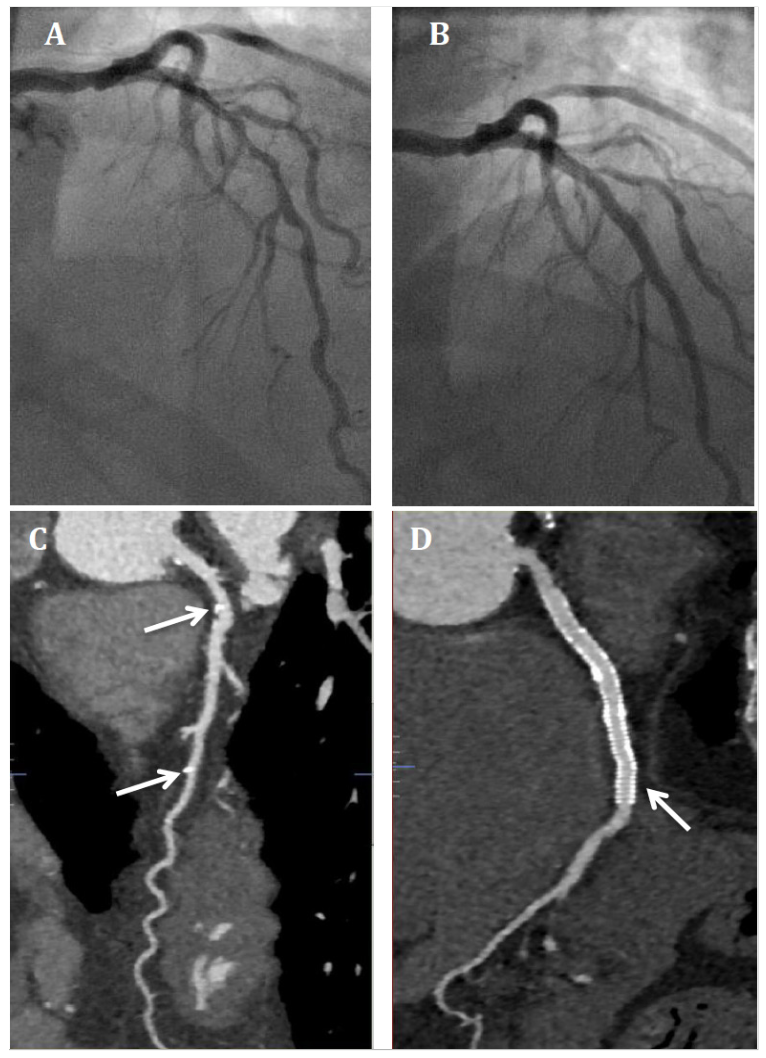

A 72-year-old gentleman presented with angina. He had previously undergone percutaneous coronary intervention (PCI) to the right coronary artery and left circumflex artery (LCX) with drug-eluting stents. Coronary angiography revealed a long segment of moderate stenosis in the proximal to mid left anterior descending artery (LAD) (Figure 1A). This was treated with Absorb bioresorbable vascular scaffolds (BVS; Abbott Vascular) (Figure 1B) with the use of intravascular ultrasound to confirm adequate stent expansion. He represented 5 years after his PCI with atypical symptoms. A computed tomography coronary angiogram showed the BVS were no longer visible and only the platinum markers were seen (Figure 1C). The scaffolds had been completely reabsorbed, allowing the use of non-invasive imaging to obtain high-quality diagnostic images not affected by artefact, as seen with the DES in the LCX (Figure 1D) preventing the vessel being assessed with the same clarity.